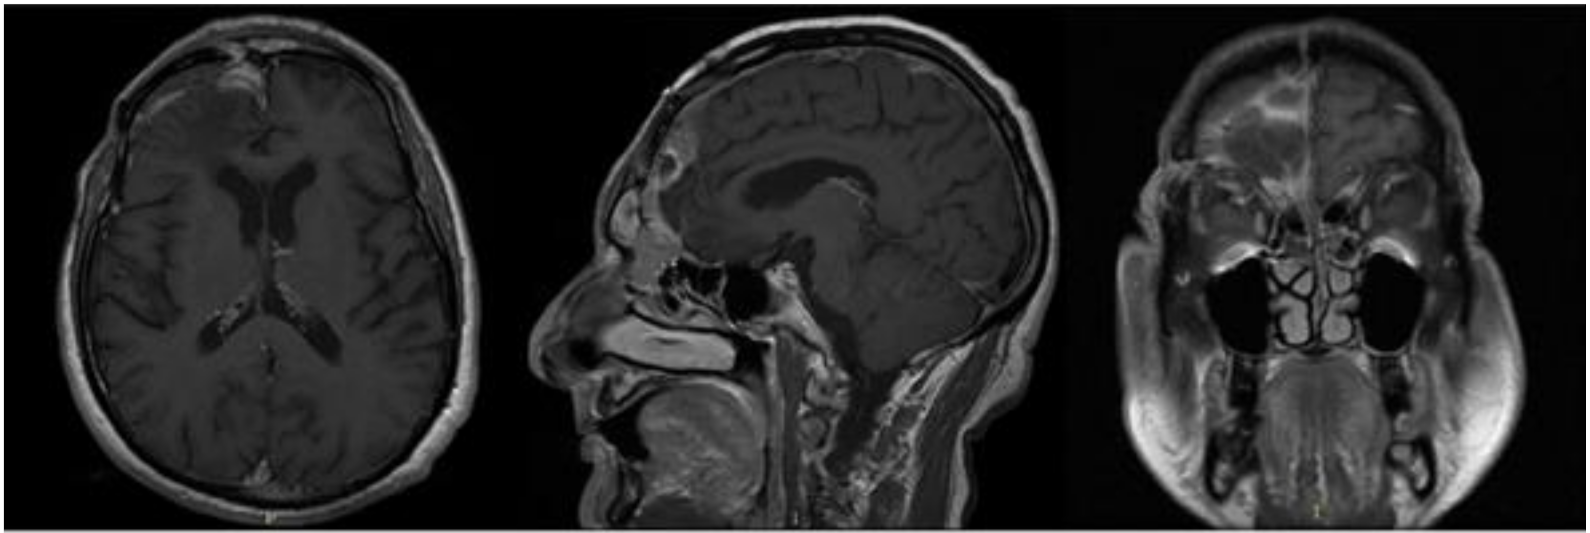

In September 2017, the patient came to our attention with frontal headache, pyorrhea, right eye swelling, fever and general weakness. The MRI documented the recurrence of the tumor and an evident epidural empyema (Figure 4). We performed tumor resection and revision of the surgical cavity; the titanium mesh was replaced with autologous fascia lata. Frontal operculum was definitively removed.

Figure 4.

Brain MRI with evidence of a right frontal epidural empyema and meningioma recurrence (left, DWI; center, T1-weighted with contrast; right, T2-weighted).